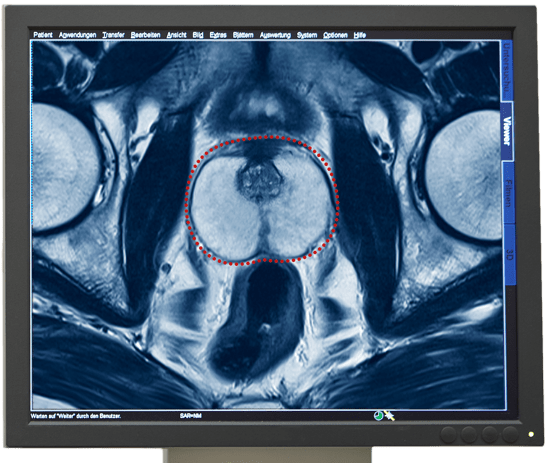

Vroegtijdige en zekere diagnose door multiparametrisch MRI-onderzoek van de Prostaat

Het multiparmetrisch MRI-onderzoek van de Prostaat geldt als het zekerste beeldmateriaal om prostaatkanker te diagnosticeren. Met dit onderzoek kan een kankergezwel gevonden worden en de eigenschappen daarvan vastgesteld en beoordeeld worden.

De informatie over de kwaadaardigheid van een tumor wordt geleverd door een weefselanalyse. Daarvoor worden weefselbiopten uit het verdachte kankergezwel genomen. Met onze Prostaatbiopsie kunnen wij door MRI-sturing gerichte biopten uit het gezwel nemen, pathologisch onderzoeken en de Gleason-score bepalen.

MRI-onderzoek als basis voor adequate therapie bij Prostaatkanker

Een multiparametrisch MRI-onderzoek van de prostaat kan de volgende informatie geven, die voor de aansluitende therapie behulpzaam kan zijn.

- Diagnose van de kwaadaardige tumor

- Plaats van de tumor

- Bepaling van de grote en volume van een tumor

- Expansie van de tumor

- Eventuele aantasting van de omliggende structuren of organen

- Eventuele aantasting van de lymfeknopen in het bekken

- Eventuele aanwezigheid van uitzaaiingen in de bekkenbeenderen